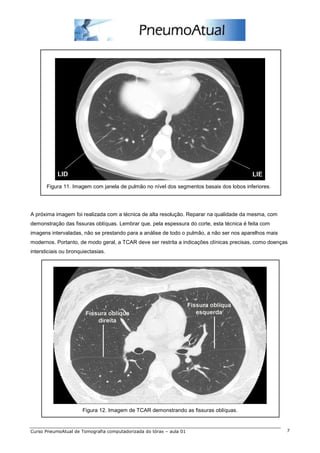

Figura 11. Imagem com janela de pulmão no nível dos segmentos basais dos lobos inferiores.

A próxima imagem foi realizada com a técnica de alta resolução. Reparar na qualidade da mesma, com

demonstração das fissuras oblíquas. Lembrar que, pela espessura do corte, esta técnica é feita com

imagens intervaladas, não se prestando para a análise de todo o pulmão, a não ser nos aparelhos mais

modernos. Portanto, de modo geral, a TCAR deve ser restrita a indicações clínicas precisas, como doenças

intersticiais ou bronquiectasias.

Figura 12. Imagem de TCAR demonstrando as fissuras oblíquas.